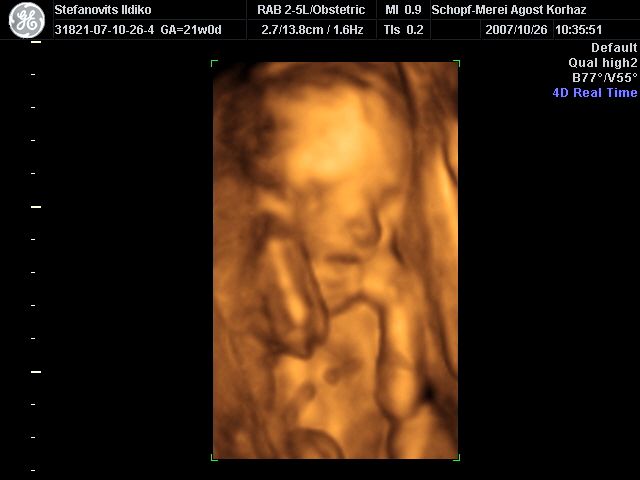

4D Ultrahang - 21+1 (07/10/26, Bp.)

4D - 7